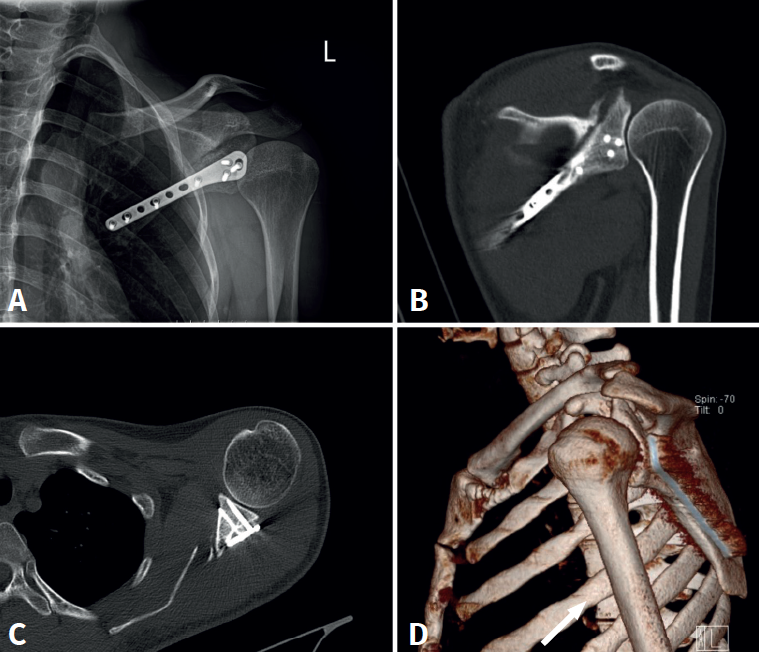

En el postoperatorio se realizan radiografías simples para comprobar la correcta reducción y síntesis de la fractura, y a los 2 meses se realiza una TC para controlar el proceso de consolidación y cerciorarse de que no existen tornillos intraarticulares (Figura 6).